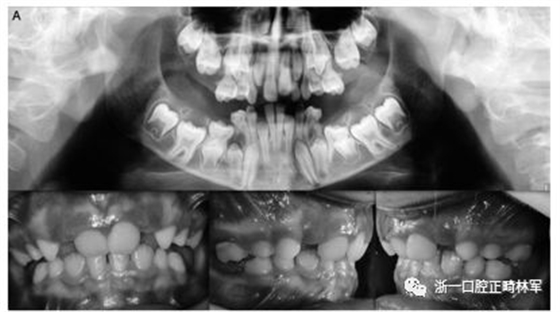

最后,在数据库中以前没有报道的错义变体在外显子16 c.1765 T>C p.Trp89Arg中发现。 在同一家庭的三个成员 - 母亲,女儿和儿子(图3A,B)中发现的错义变体-负责用精氨酸p:Trp89Arg取代氨基酸色氨酸,这是一种具有不同化学特性的氨基酸。该突变发生在PTH1R蛋白质的胞质结构域中,并参与受体与激活细胞内级联信号的G蛋白的相互作用。此外,计算机结果表明,PTH1R蛋白质中的这种氨基酸取代改变了蛋白质的结构和功能,因为它发生在蛋白质的催化结构域内。

图3.(A,B)两兄弟的口内照片。全景:外显子16中的家族错义变体c.1765 T>C p.589 W>R

属于2号家庭的小女儿(2:2)表现出更复杂的临床表现,缺乏永久性以及暂时性系列和囊性结构元素的萌出(图3A,B)。在哥哥(II:1;图3A,B)中发现由于包括多颗恒牙的严重的双侧后牙开合。最后,患者II:1和II:2的母亲表现出双侧上颌第一磨牙和下磨牙的包埋。发现前磨牙层面没有咬合接触(图3A,B)。

本研究中确定的低咬合的临床特征与PFE基于基因诊断和萌出障碍诊断标准的应用相一致。对特定相关牙科特征的仔细临床检查包括以下内容:至少一颗牙包括低咬合,局限于后部区域,单侧(38%;图1A)和双侧呈现(35%;图1B和2),至少有一个暂时性后牙(48%暂时;图1A,B和3A; 55%永久性,图3B)。

此外,观察到牙面特征如下:由于受影响侧的侧向开放咬伤的严重程度而引起的垂直骨骼不对称(35%;图1A,B和图3A,B);由下颌骨侧向偏离组成的面部不对称(图1A,B和图2;表4)。

这种不对称在单侧开合患者中更为明显。进一步发现受影响的患者与先前报道的患者存在上颌骨收缩和III类牙齿/骨骼关系(28%;图1A,B和图2)。至少有一例患者出现了相对于9名患者的低咬合。表4总结了PTH1R的表型结果和相关的突变分析(N = 8)。